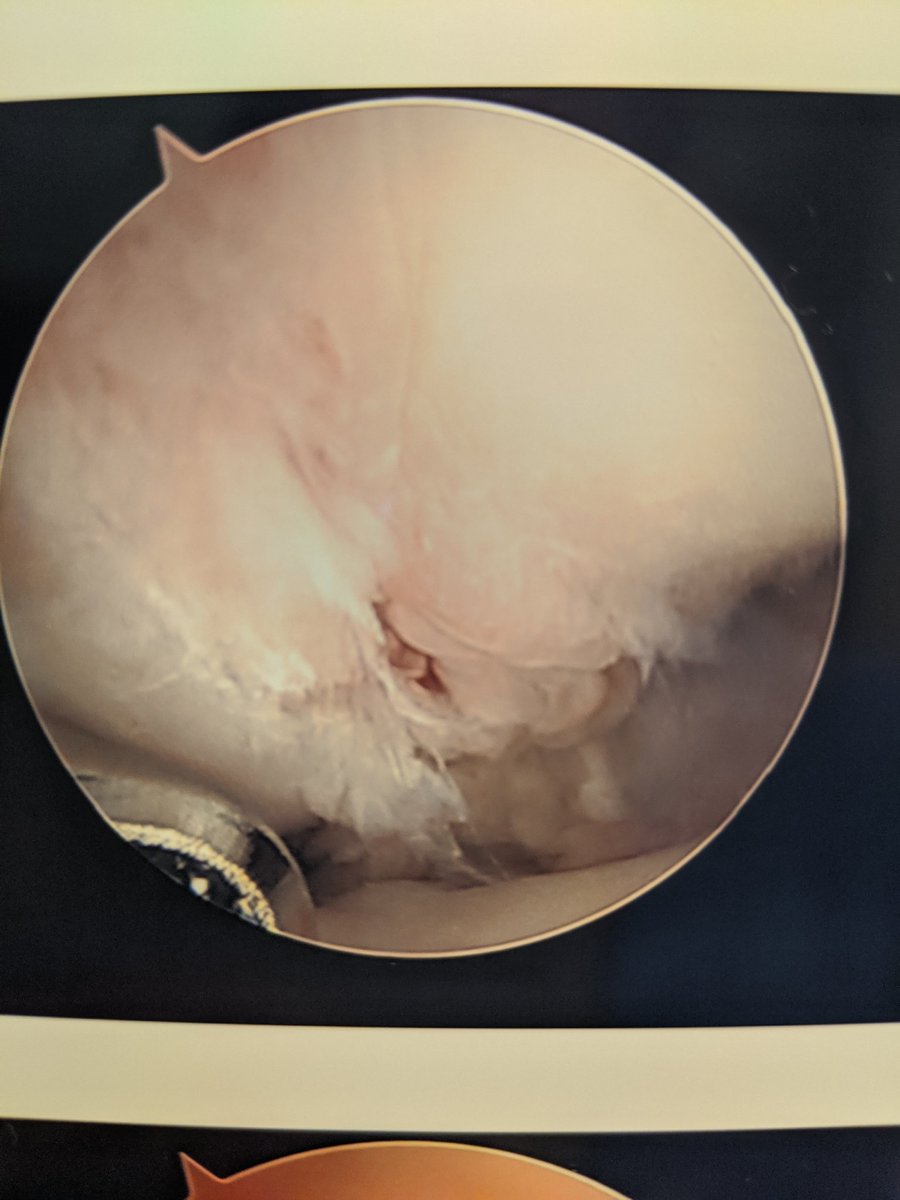

Of course, the scope tower saved whichever images it felt like. Membranous SL tear, no drive through, no shuck.

Scope assisted reduction of the articular surface was pretty cool, but radiographs honestly showed the same story

Debrided and pinned the SL